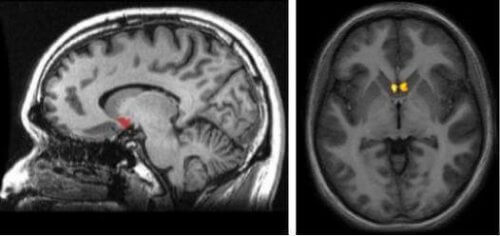

Il y a un noyau accumbens dans chaque hémisphère cérébral qui donne forme à un système complexe de récompense. Grâce à lui, nous ressentons du plaisir, nous apprenons de nouvelles choses et nous trouvons la motivation au quotidien.

Chaque hémisphère cérébral a son noyau accumbens. De cette façon, le système de récompense orchestré par la dopamine atteint chaque aire du cerveau. Il s’agit aussi d’une structure qui fait partie des dénommés ganglions basaux. Ainsi, et même si à première vue, le noyau accumbens semble être assez petit, il se caractérise surtout par sa grande connectivité.